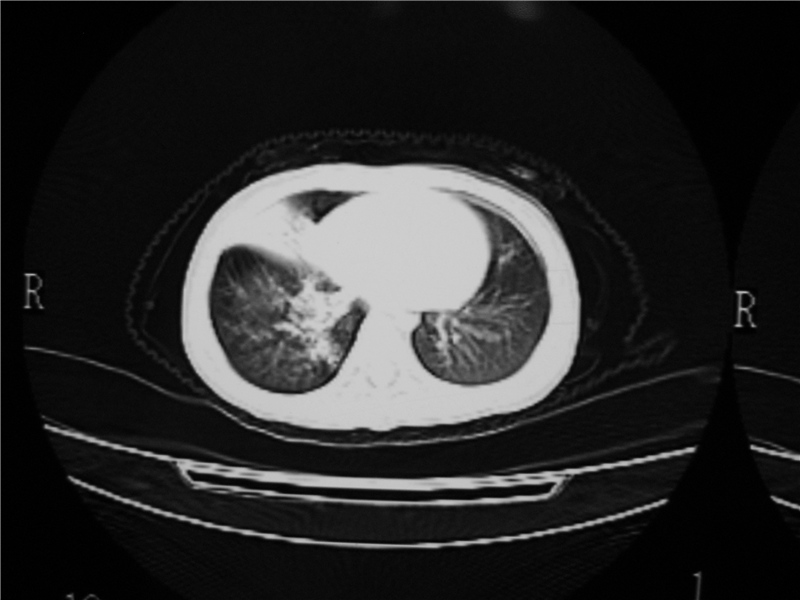

标题: PED3236:男2岁进食花生米后发烧10天。

右肺中叶及下叶内段大片实变密度增高影,可见支气管气象,肺炎.

摄吸气及呼气相对比片,本例为有肺中叶阻塞性炎症、不张,右肺下叶阻塞性炎症。

1)右肺炎症并右肺中叶肺不张,右肺上叶充气不良。2)右侧支气管异物不排除。

结合临床考虑支气管异物并阻塞性肺炎、肺不张。